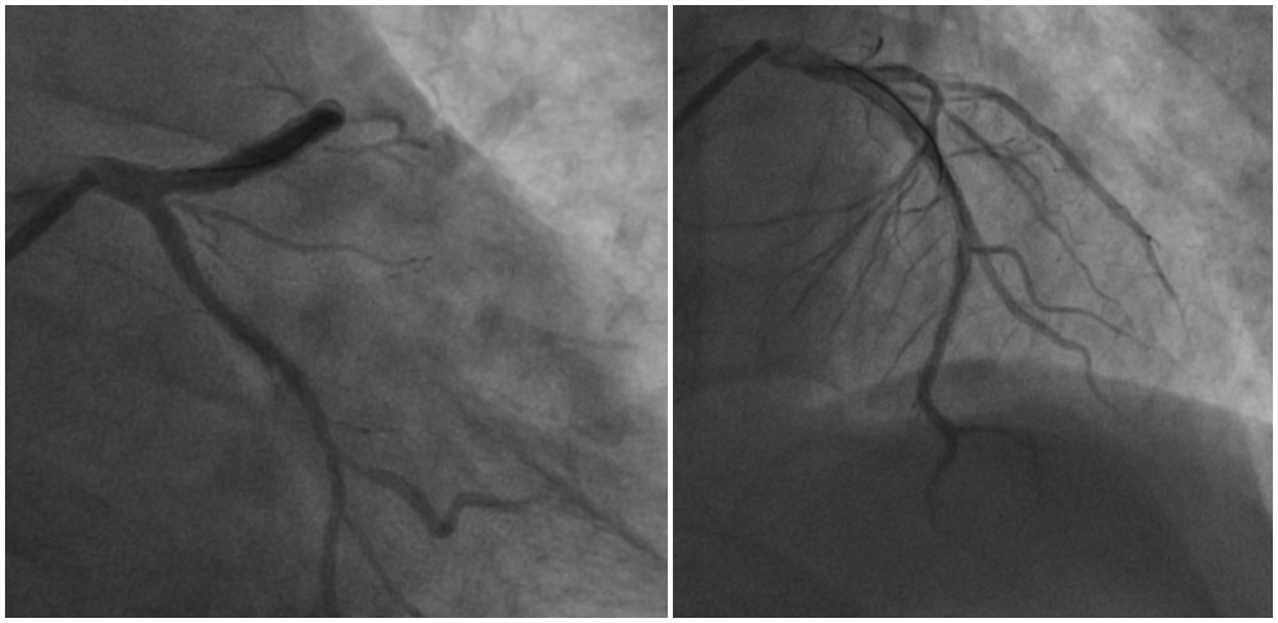

“王哥,这是下壁心肌梗死,右冠闭塞是罪犯血管啊。”助手有些紧张的问“这我能不知道?!”王乂的声音不大,但是有些吓人,尤其是那双眼睛,快要喷出火来。一时间,再没人敢说话,只看到王乂不断操作:LAD病变处2.0*15mm球囊以12atm预扩张,造影后可见残狭减轻,血流改善,LCX血流也同时改善,均达TIMI3级。将3.5*14mm支架至LAD病变处以16atm扩释,造影后未见明显残余狭窄及夹层,前向血流TIMI3级。(图3)

图3. 左冠术后状况

再处理RCA,王乂就从容了很多:RCA两支架间次全闭塞,送2.0*15mm球囊至远端病变处以12atm预扩,造影可见残狭减轻,PD近段90%狭窄,2.0*15mm球囊12atm扩张PD近段,造影血流减慢,冠脉应用替罗非班15ml、尼可地尔400μg后血流TIMI3级。再送3.0*14mm支架至RCAp病变处以18atm扩释,前向血流TIMI3级。(图4)

图4.右冠术后状况